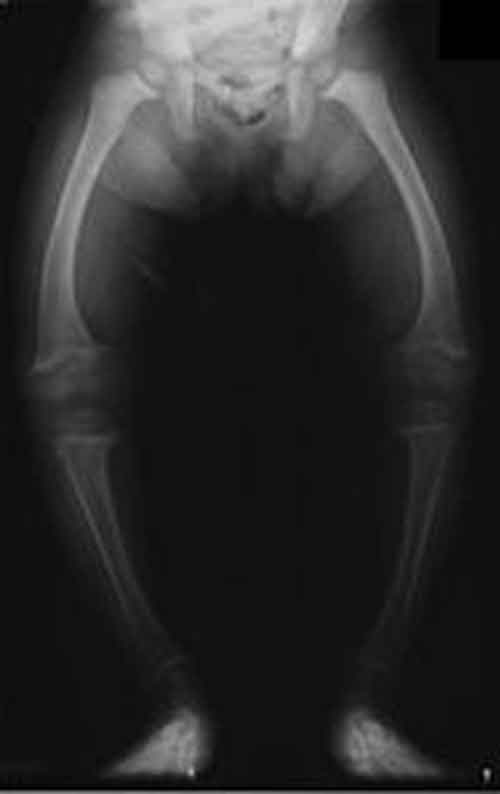

Un nuovo studio della McGill University ha scoperto il ruolo fondamentale dell’osteopontina, una proteina del substrato di denti ed ossa, nella forma piu’ comune di rachitismo ereditario, il rachitismo ipofosfatemico legato all’X (XLH).rachitismo In questa patologia, i bambini sono di bassa statura, essenzialmente a causa della deformazione ad arco degli arti inferiori, e presentano una ridotta mineralizzazione ossea. A quanto si legge sul Journal of Bone and Mineral Research, gli scienziati hanno scoperto che l’attivita’ enzimatica del gene PHEX, le cui mutazioni possono portare alla XLH, causano una essenziale diminuzione e una quasi totale assenza dell’osteopontina nelle ossa.

L’osteopontina, permette normalmente la rimineralizzazione di ossa e denti e li indurisce per soddisfare le esigenze biomeccaniche a cui sono sottoposti. Nei pazienti affetti da XLH, privi dell’ enzima PHEX, viene impedito l’indurimento dell’osso e si hanno cosi’ ossa morbide e deformate, che generano disturbi come le gambe arcuate.